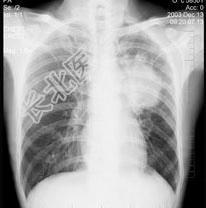

- 单项选择题女性,51岁, 胸痛数月,痰血两天, X线检查见图,最可能的诊断是 ( )

A、左肺癌

B、左侧炎性假瘤

C、左侧纵隔肿瘤

D、左肺转移瘤

E、支气管扩张